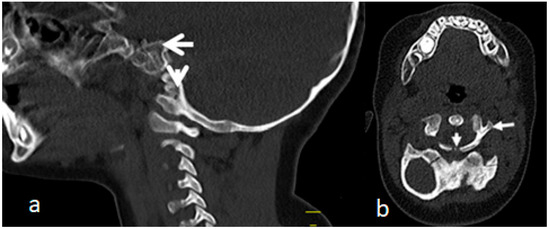

A 3D-reformatted sagittal CT scan of the cranium shows a six-month-old-child who was born with congenital tetraplegia. Maldevelopment of the anterior ring of the atlas C1, which has been displaced along the superior surface of the clivus, is also evident. Also, the (odontoid process is hypoplastic and dislocated and 9s located between the maldeveloped anterior rings) (arrow head). Fusion of the fragmented anterior and posterior rings of C1 and fusion of these fragments effect the development of a bifurcation-like structure (Figure 4a). An axial 3D-reformatted CT scan shows congenital maldevelopment of the anterior arch of the atlas and fusion of the remnants of anterior ring with the lateral mass of C1 (forming a Y-shaped deformity) (arrow head). The posterior ring of C1 is hypoplastic, resembling a Jefferson fracture (arrow head) (Figure 4b).

Figure 4.

(a,b). A 3D-reformatted sagittal CT scan of the cranium in a six-month-old child with Larsen syndrome who was born with congenital tetraplagia. Note the maldevelopment of the anterior ring of the atlas C1, which has been displaced along the superior surface of the clivus. Also, the odontoid process is hypoplastic and dislocated and displaced between the defectively developed anterior rings (arrow head). Fusion of the fragmented anterior and posterior rings of C1 and fusion of these fragments causing effectively the development of a Y-shaped deformity (a). Axial 3D-reformatted CT scan showing congenital maldevelopment of the anterior arch of the atlas and fusion of the remnants of the anterior ring with the lateral mass of C1 (forming a Y-shaped bone deformity) (arrow head). The posterior ring of C1 is hypoplastic resembling a Jefferson fracture (arrow head) (b).